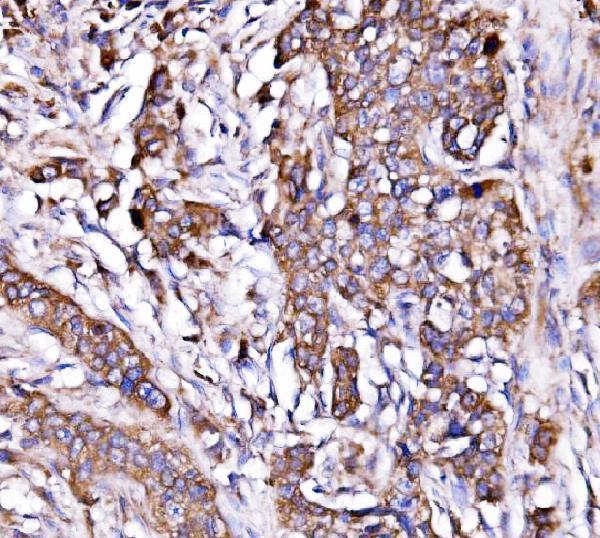

IHC analysis of ORP150/HYOU1 using anti-ORP150/HYOU1 antibody (A04934-2).

ORP150/HYOU1 was detected in a paraffin-embedded section of human hyroid papillary carcinoma tissue. Heat mediated antigen retrieval was performed in EDTA buffer (pH 8.0, epitope retrieval solution). The tissue section was blocked with 10% goat serum. The tissue section was then incubated with 2 μg/ml rabbit anti-ORP150/HYOU1 Antibody (A04934-2) overnight at 4°C. Biotinylated goat anti-rabbit IgG was used as secondary antibody and incubated for 30 minutes at 37°C. The tissue section was developed using Strepavidin-Biotin-Complex (SABC) (Catalog # SA1022) with DAB as the chromogen.